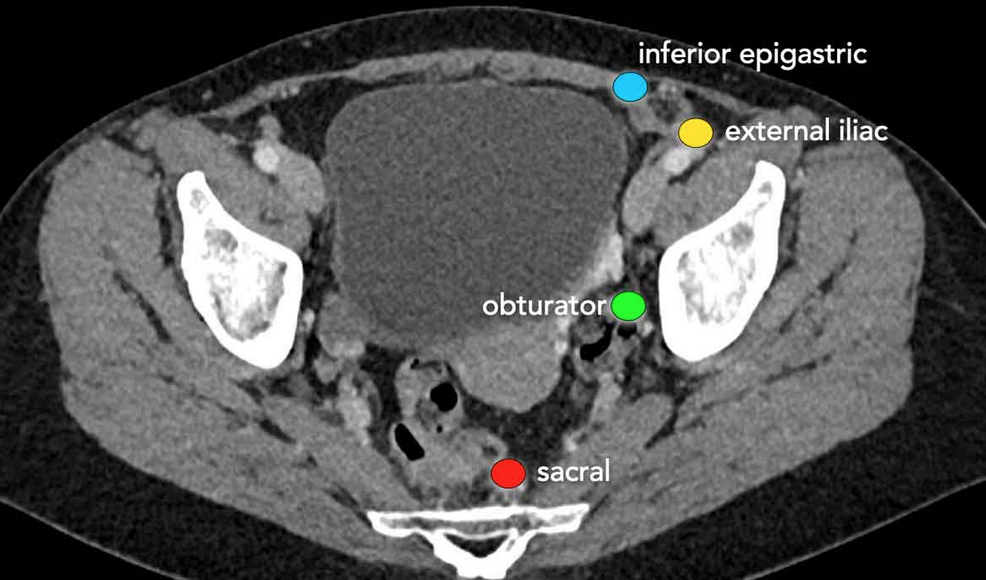

• LN involvement

• Pelvic sidewall invasion is the mass within 3 mm of one of the following

• Levator ani muscle

• Piriformis muscle

• Internal obturator muscle

• Iliac vessels